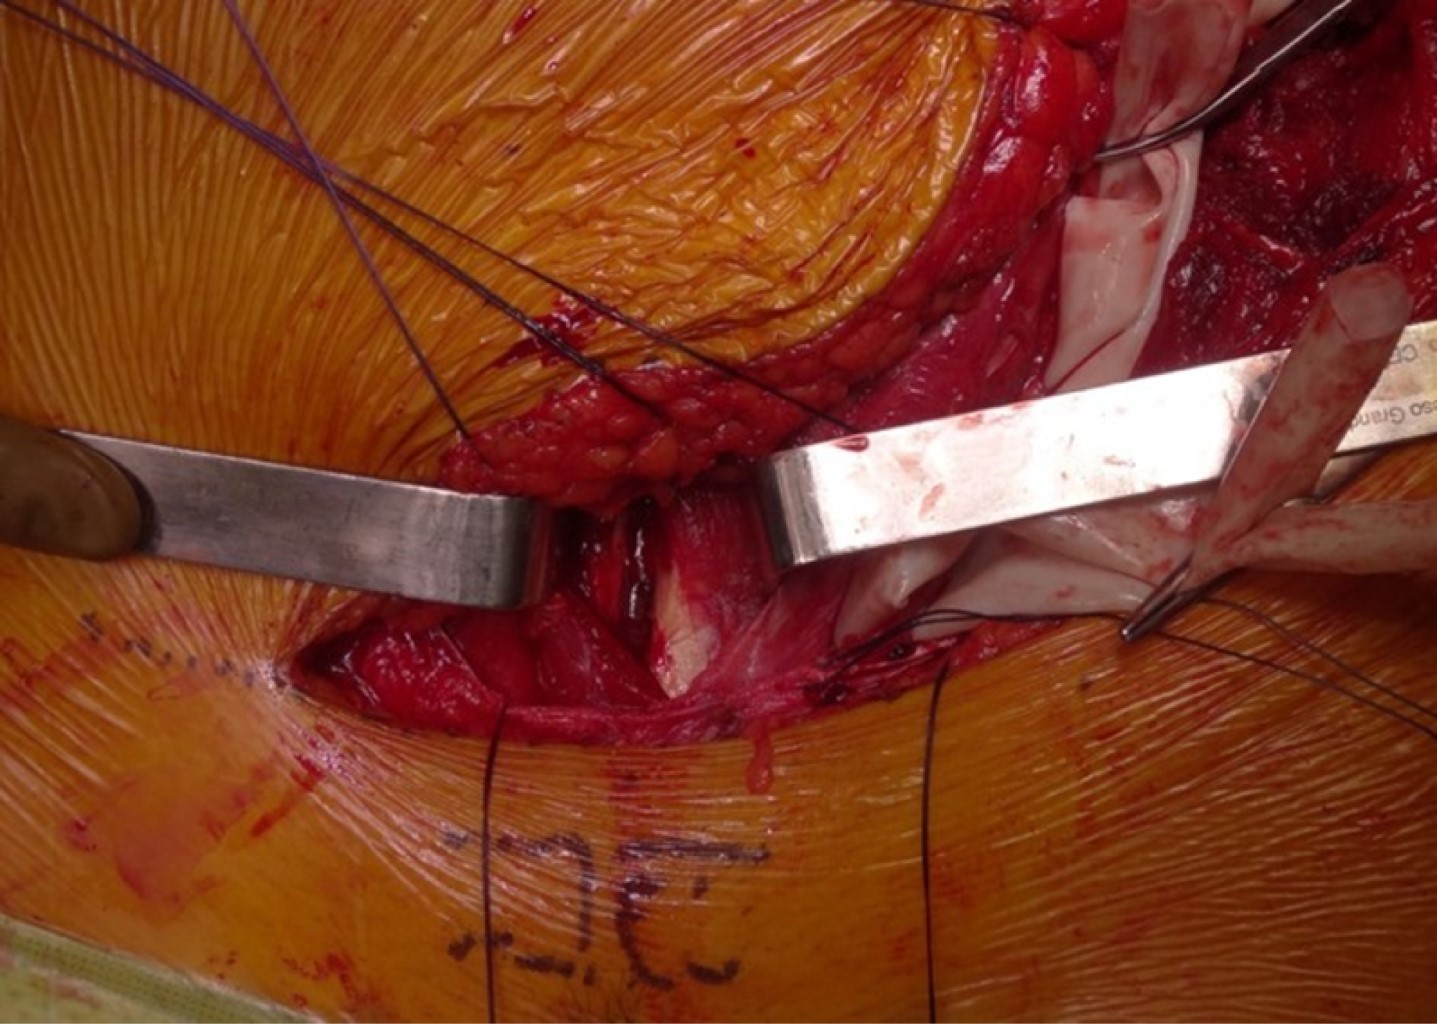

Lo más común es realizar la primera ventana, la más lateral, primero. Sobre la cresta ilíaca proximal a la espina ilíaca anterosuperior, se identifica la zona de transición entre los abductores de la cadera y los músculos abdominales. Se incide sobre la cresta y se separan subperiósticamente los músculos abdominales y el músculo ilíaco hacia proximal, exponiendo la fosa ilíaca. Esto se logra desplazando la masa muscular con un separador de Cob y colocando a la vez una compresa quirúrgica que facilita la disección. De encontrarse vasos comunicantes sangrando en la superficie del ilíaco puede utilizarse cera para hueso para la hemostasia. Palpando y con visión directa se puede exponer desde la articulación sacroilíaca hasta el reborde pélvico proximal y a la escotadura ciática. La fosa ilíaca permanece empaquetada con la compresa y se procede a la realización de la segunda y más compleja ventana (Figura 3).

Techo del canal inguinal: formado por el oblicuo externo. Se inicia una incisión sobre la fascia del oblicuo externo justo sobre la espina ilíaca anterosuperior en continuidad con la trayectoria de la incisión de la primera ventana. Continúa sobre la fascia del oblicuo externo, siguiendo el trayecto de sus fibras 2 a 3 cm proximalmente al ligamento inguinal dirigido hacia medial y llagando 2 cm proximales al anillo inguinal externo (Figura 4). Se incide la fascia del oblicuo externo entre el anillo inguinal y espina ilíaca, descubriendo el canal inguinal y su contenido. Debe identificarse el nervio ilioinguinal. Se refieren los bordes libres de la fascia en los segmentos proximal y distal en las porciones medial y lateral con suturas para su reparación al cierre.

Figura 3

Figura 4